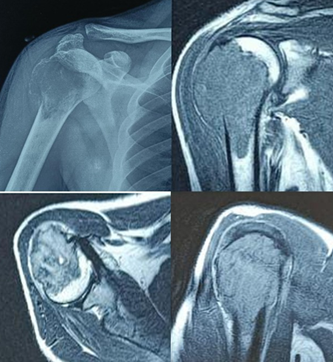

We present a case of a 30-year-old male who presented to the hospital with complaints of pain and restricted range of movement in the right shoulder since 3 months following a trivial trauma. Examination revealed bony-hard swelling, tenderness over the lateral aspect of shoulder, no signs of inflammation with restricted shoulder range of motion. No distal neurovascular deficit was found. Initial radiograph at local hospital revealed an incidental finding of an expansile, lytic lesion in epiphyseo-metaphyseal region of the right proximal humerus. Further radiological investigation in the form of magnetic resonance imaging revealed a Campanacci Grade 3 osteoclastoma with an evident cortical breach (Fig. 1). Patient was planned for a biopsy of the lesion, and histopathologic investigation confirmed the diagnosis. Blood investigations revealed the patient was seropositive for Hepatitis B, but were otherwise non-contributory.

Figure 1: Pre-operative scan showing an expansile lytic lesion with a characteristic soap bubble appearance, with a cortical breach and tumor extending into the deltoid muscle.